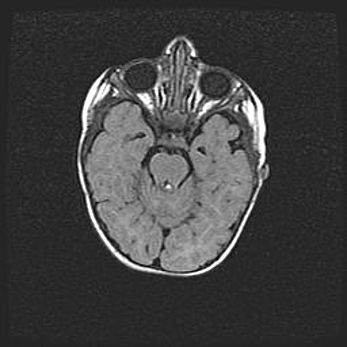

Аномалия Денди-Уокера. Признаки гипоплазии мозолистого тела.

Возраст: 5 месяцев 3 дня

Вес: 5550 г

Пол: мужской

Окружность головы: 39 см

Срок гестации: 40 недель

Аномалия Денди-Уокера – это порок развития головного мозга, для которого характерна триада симптомов: гипотрофия или аплазия червя мозжечка и/или полушарий мозжечка, расширение четвёртого желудочка с формированием ликворной кисты задней черепной ямки, гипертензионная гидроцефалия различной степени.

Гипоплазия мозолистого тела относится к дефектам внутриутробного этапа развития мозговой ткани, возникающим в процессе закладки структур головного мозга, что происходит на начальных этапах развития эмбриона.